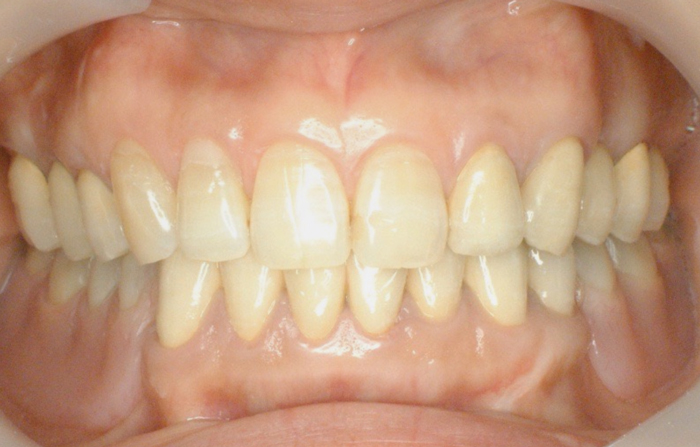

| ●本ケースは、上下顎全歯で患者さんの天然歯が4歯だけ残った症例でした。 結局、上顎にはメタルセラミックスブリッジ補綴を施し、下顎はチャネルショルダーアタッチメントと エクストラコロナル・自家製棒状アタッチメントによるミリング・コンビネーションデンチャーを装備 しています。 ●チャネルショルダーアタッチメントおよび棒状アタッチメントのテクニックに関しては「論文」編 のPDFファイルをご参照くださいませ。 また、製作工程の詳細は「臨床例:補綴用実践的ワックスアップ手順を追う! (コンビ01)」 に良く似た症例を掲載しましたので、ご供覧ください。

| ●下顎右大小臼歯から左犬歯まではメタルセラミックスの連続冠で補綴し、 右大小臼歯、右犬歯および左犬歯、左側切歯の4歯の舌側面にチャネルショルダー内冠 と棒状アタッチメントをミリング加工した。 チャネルショルダー外冠および棒状アタッチメントはパラレルミリング加工しているので、 精密な摩擦抵抗力を持った適合精度が求められます。 内冠の長径および幅径によっても、鋳造システムによる埋没工程の混液比や混水比が 変わってきますので、「コンビネーション用のチェックリスト」を制作し、データを分析しよう。